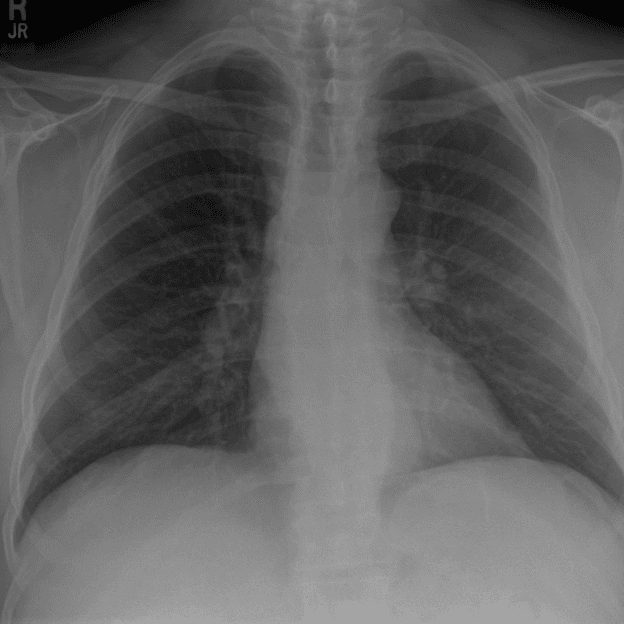

Practice Cases